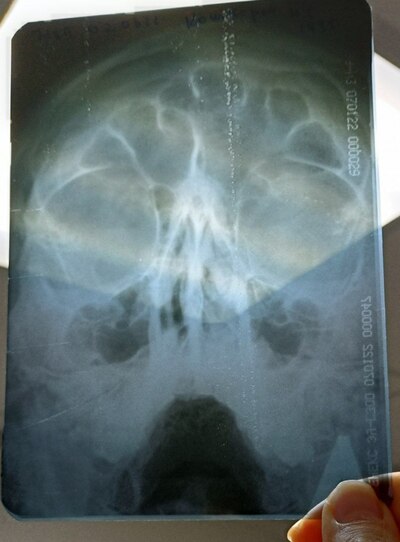

-- Понятно, почему она не дышит. -- сказал ЛОР заглянув в ту ноздрю, которая у меня хоть как-то дышит. Выяснилось, что моя перегородка искривлена так, что усложняет дыхание обеими ноздрями.

Это была моя норма жизни. Во сне и во время физических нагрузок всегда дышал ртом. На операцию я решился благодаря брату, который её сделал годом раньше. С его слов, ничего страшного и почти бесплатно. Погуглив я узнал, что кривая носовая перегородка может быть причиной большого списка последствия. Эх, была не была!

Бесплатно делают там же, где платно, поэтому я выбрал первый вариант. Обычный ЛОР по ОМС даёт направление на КТ и на предоперационную комиссию. Чтобы ускорить, я пошёл на платную комиссию за 3 т.р. Операция была назначена через 2 месяца. Платная за 100 т.р. тоже не раньше.